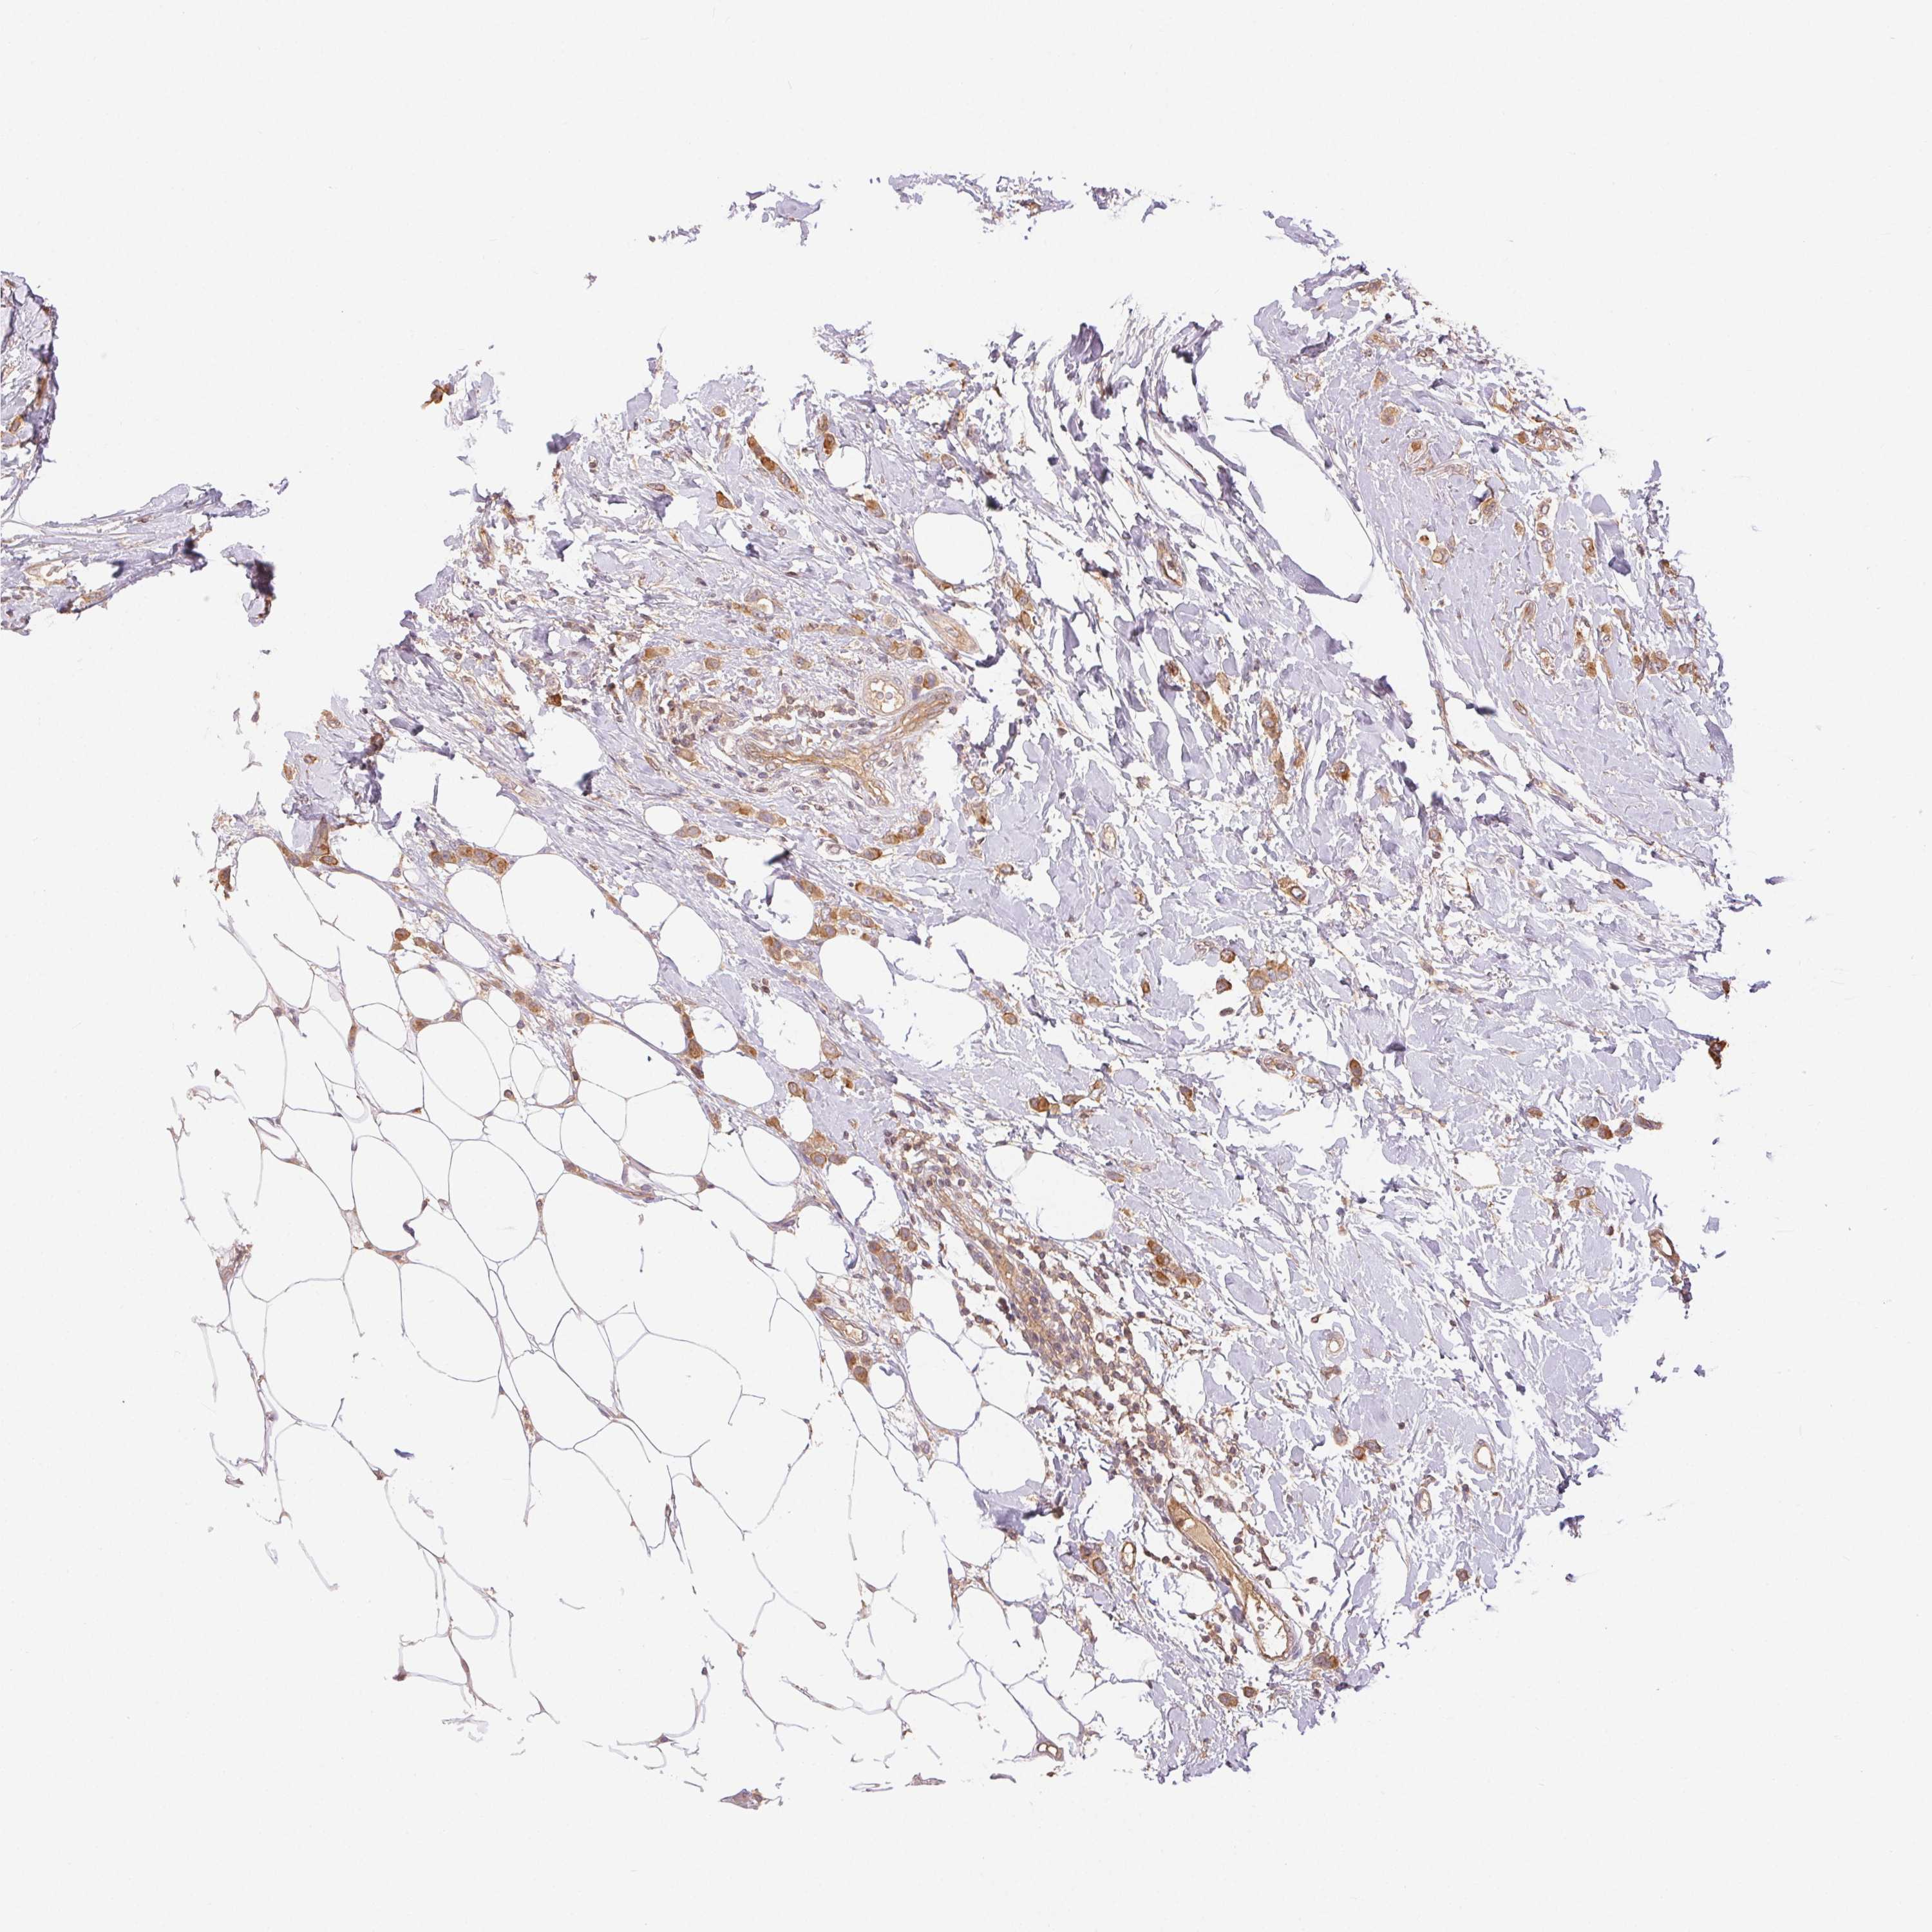

CANCER BREAST CANCER Show tissue menu

BRCA TCGA BRCA VALIDATION PROTEIN EXPRESSION

Breast cancer

Human cancer